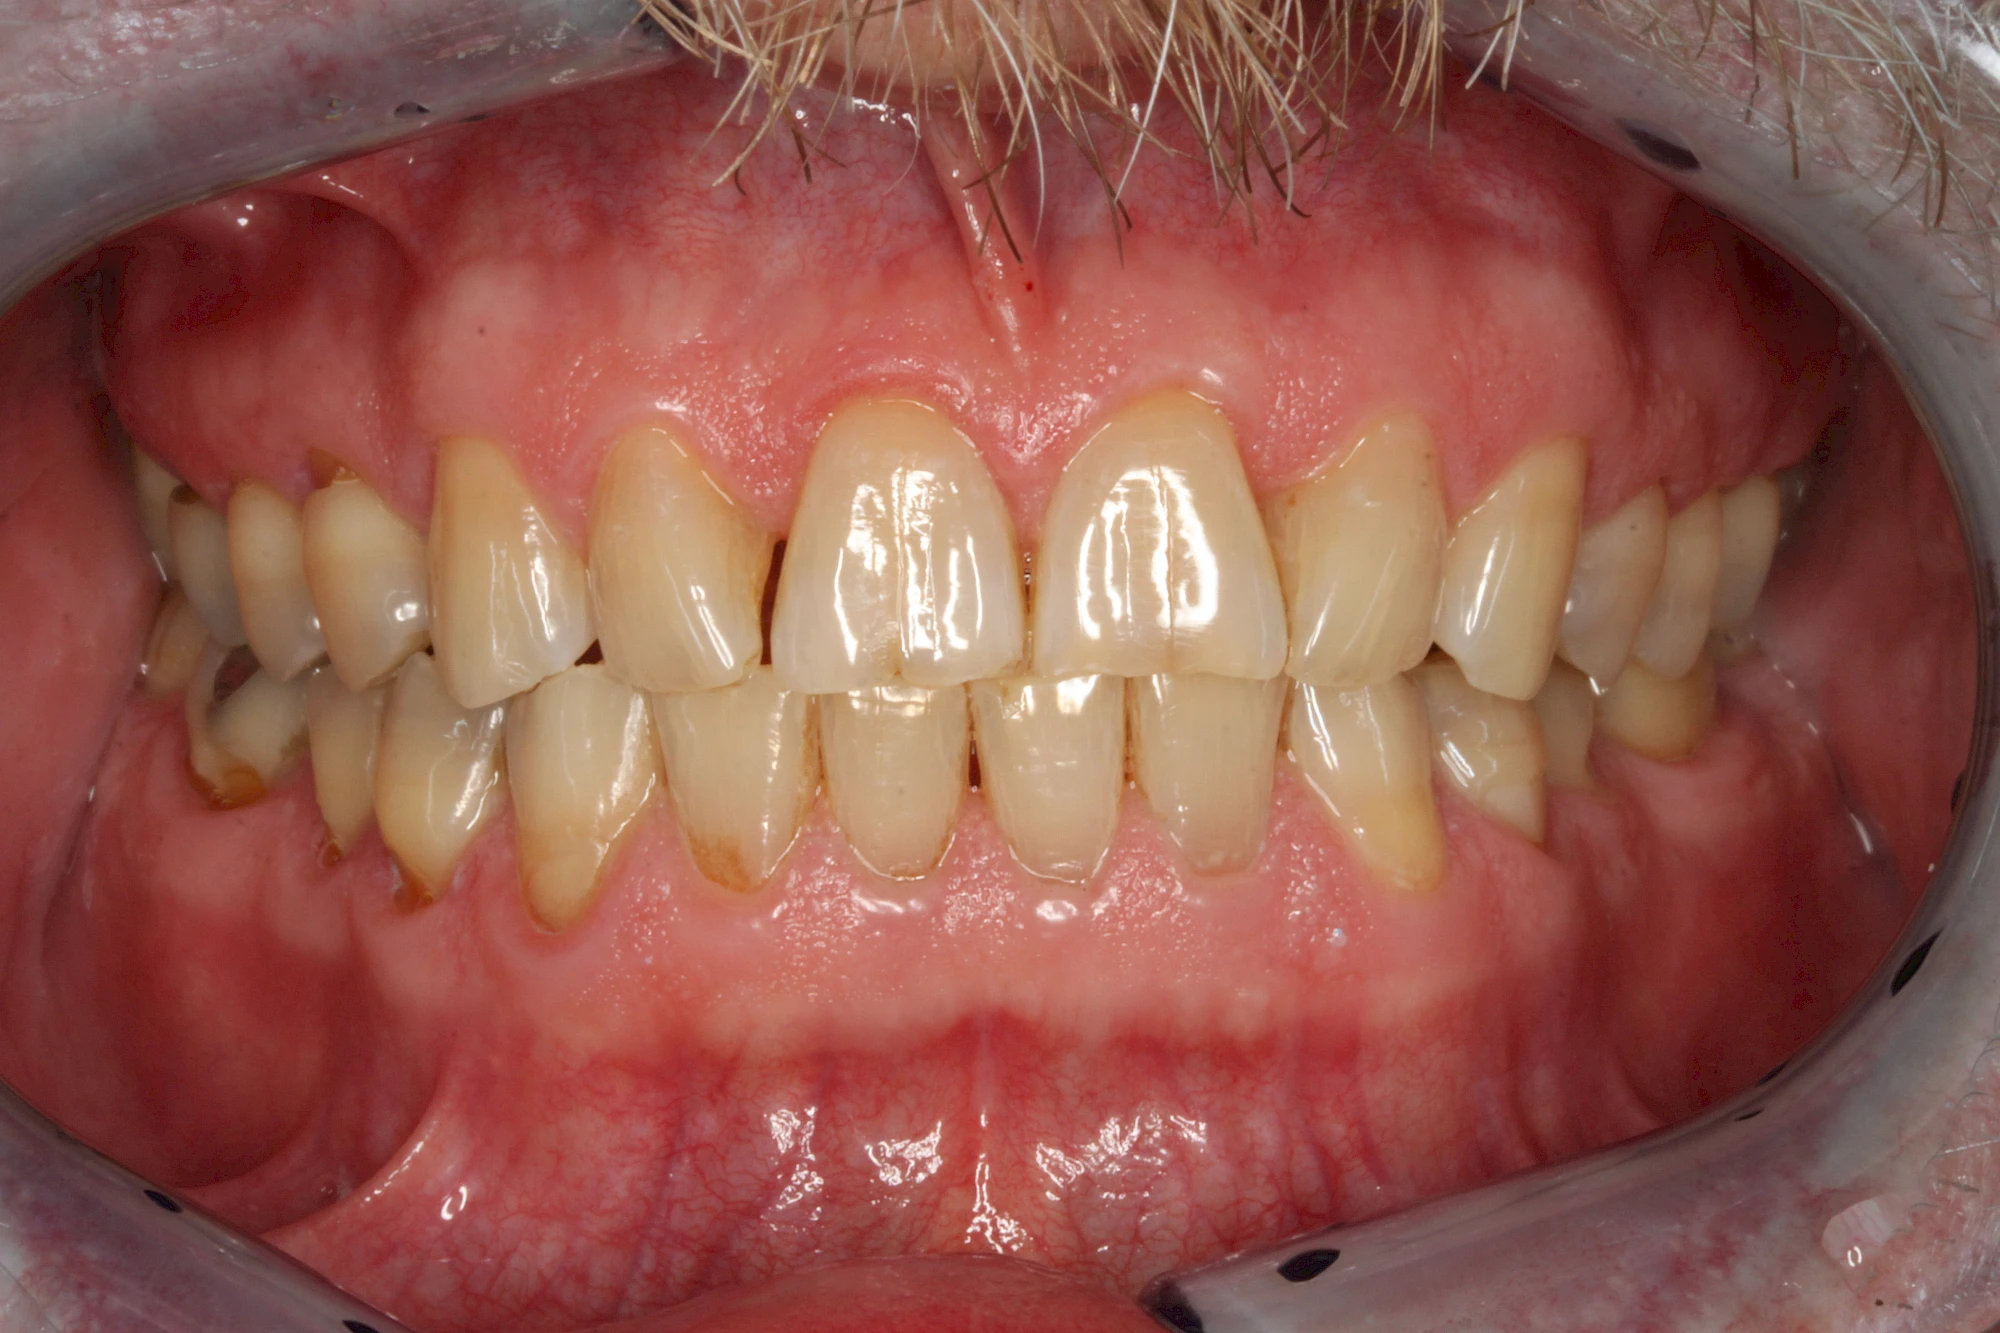

Über die Zeit können verschiedene Prozesse die Zahnhartsubstanzen aufzehren:

- Abnutzung durch Kauen (Abrasion) oder duch durch übermäßiges Knirschen bzw. Pressen (Attrition)

- Säurebedingte Auswaschung (Erosion)

- Knirschen bzw. Pressen und ungünstige Putztechnik (Druck): keilförmige Defekte